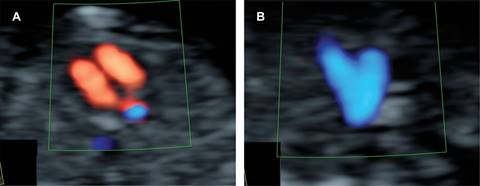

La evaluación cardiaca fetal en segundo trimestre se realiza en las semanas 18 a 24, como parte del estudio anatómico. De acuerdo con los lineamientos de la Sociedad Internacional de Ultrasonido en Obstetricia y Ginecología (ISUOG) debe incluir al menos el corte de cuatro cámaras y los tractos de salida.4 Suele agregarse el corte de tres vasos y tráquea (Figura 2).4 La evaluación integral en primer y segundo trimestre permite identificar 82.1% de las cardiopatías congénitas.6

Figura 2: Evaluación básica del corazón fetal en segundo trimestre: A) corte de cuatro cámaras; B) tracto de salida del ventrículo izquierdo; C) tracto de salida del ventrículo derecho; D) corte de tres vasos y tráquea con Doppler color.